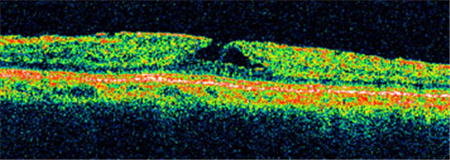

Ⅰ期黃斑裂孔通常無需手術,若裂孔惡化至Ⅱ-Ⅳ期就需要考慮進行手術治療。上海眼科醫院排名通過學相干斷層掃描來診斷黃斑裂孔,可清楚照出玻璃體及視網膜的情況,了解患者黃斑裂孔的大小、位置等。